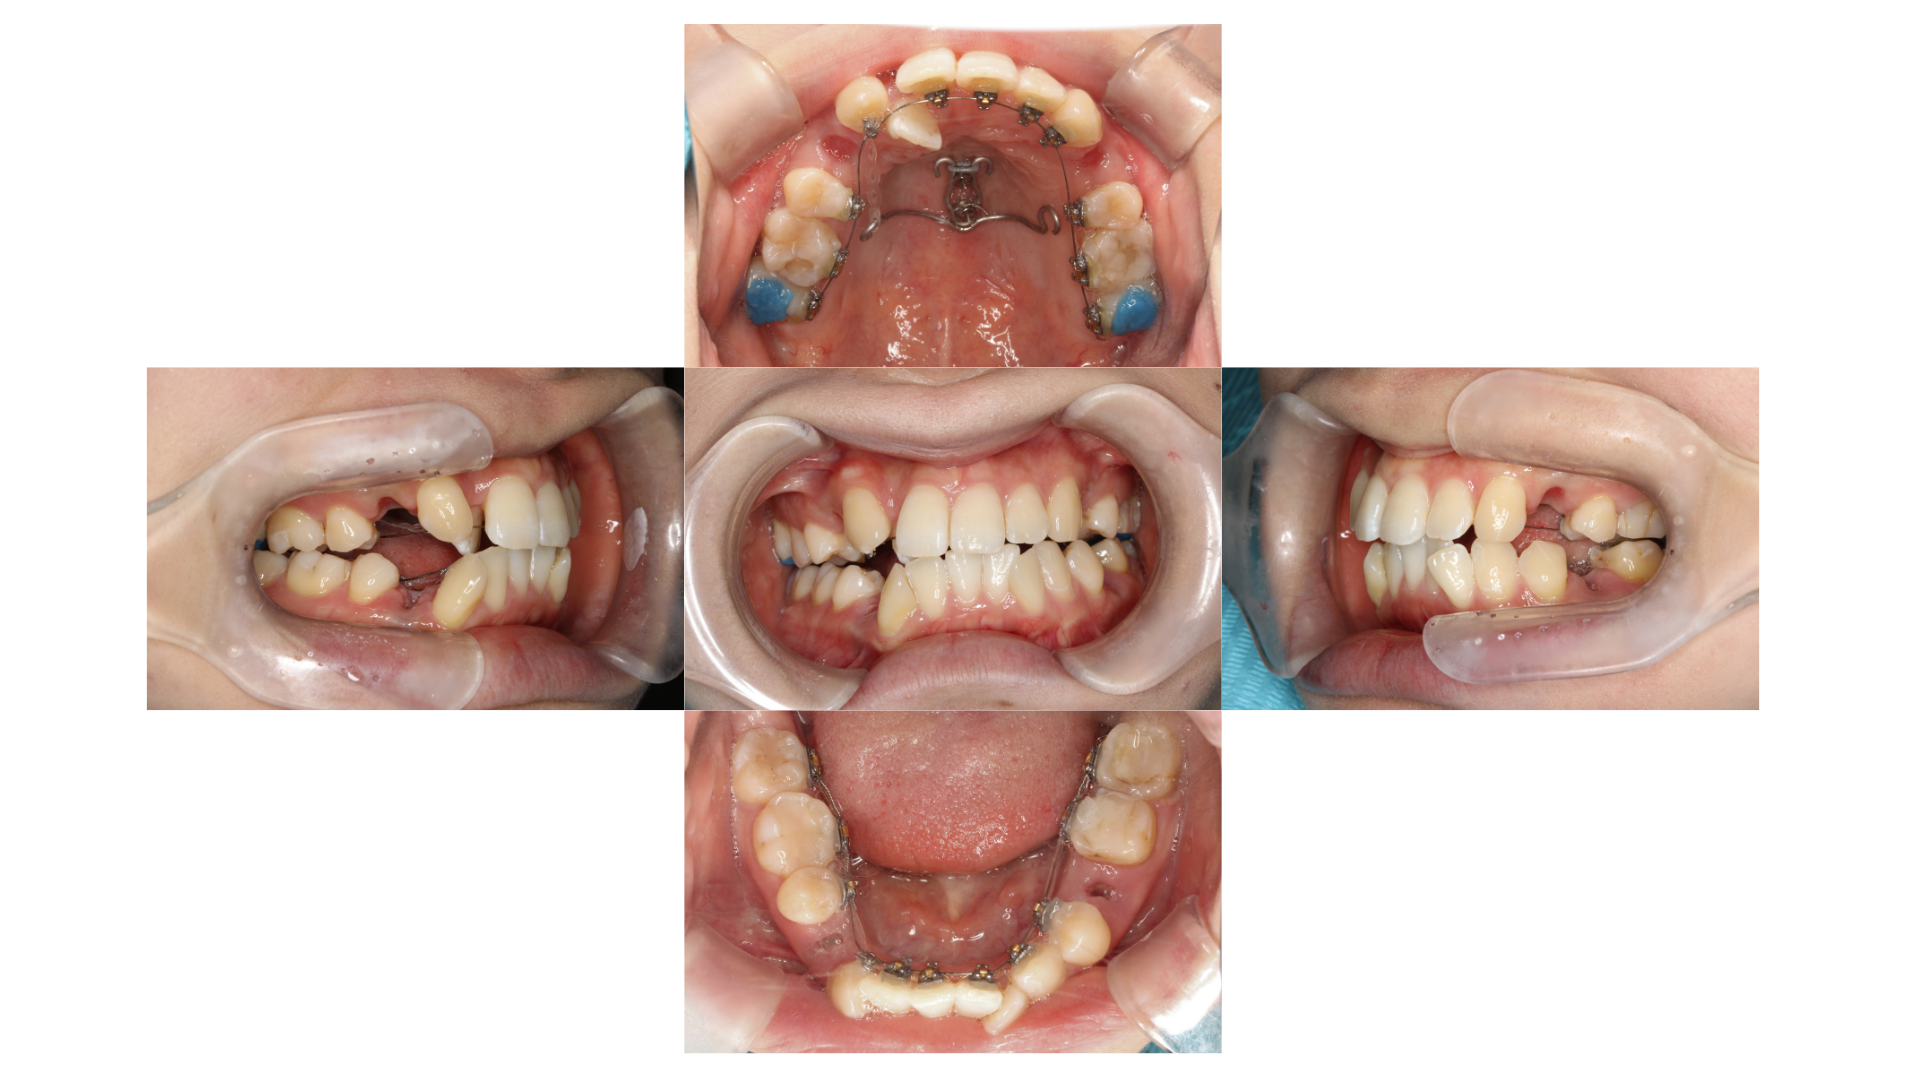

10ヵ月経過時